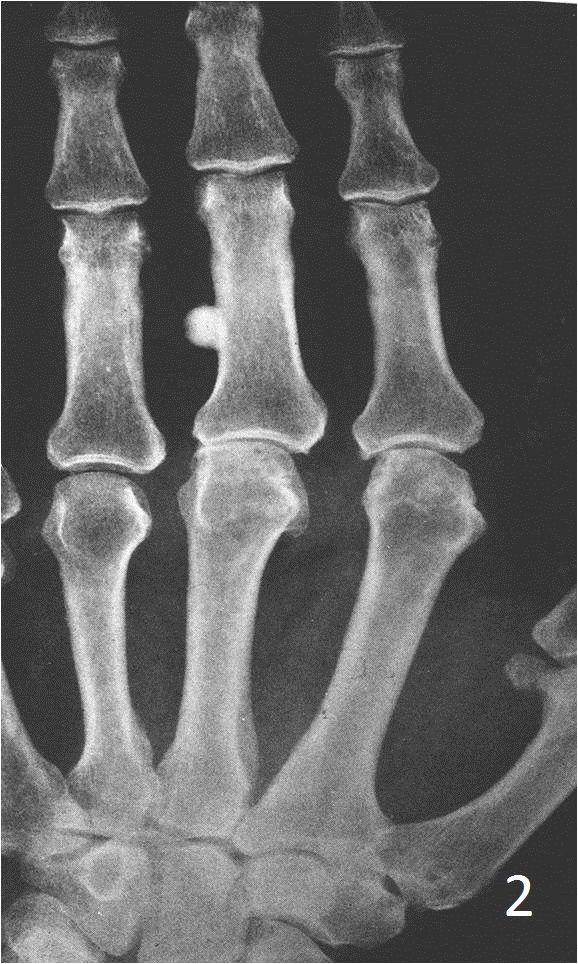

- Multiple osteomas/osteomas involving a long bone, rule out Gardner syndrome (osteomas, colon polyps and desmoid tumors)

- Sharply defined, radiopaque smooth, homogeneous bone protruding from the surface of a bone

- Almost appears as a localized thickening of the bone